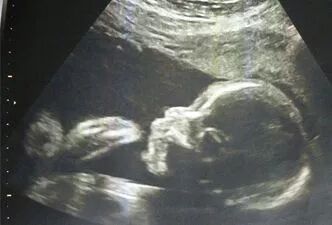

到医院做连续一个周期的卵泡B超监测。现在有不少女性卵泡长得很大,但由于卵泡壁太厚了,导致无法排卵、出现卵泡黄素化现象,自然就很难怀孕。通过卵泡B超监测不仅可以直观看到内膜变化,更能够查看卵泡是否能够正常长大并排出。